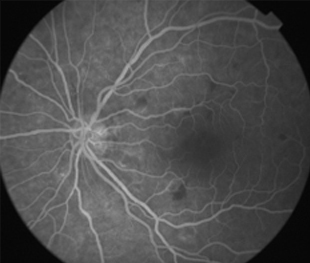

2 meses: disminución de manchas algodonosas y hemorragias con mejoría de circulación

Funcional

OD - 0,50 esf 0,9 +2

OI -0,25 esf 1,00

- Angiografía: teñido arterial, escape capilar, más tardíamente, no perfusion arteriolar y venular con teñido de las paredes vasculares y dilatación venosa.